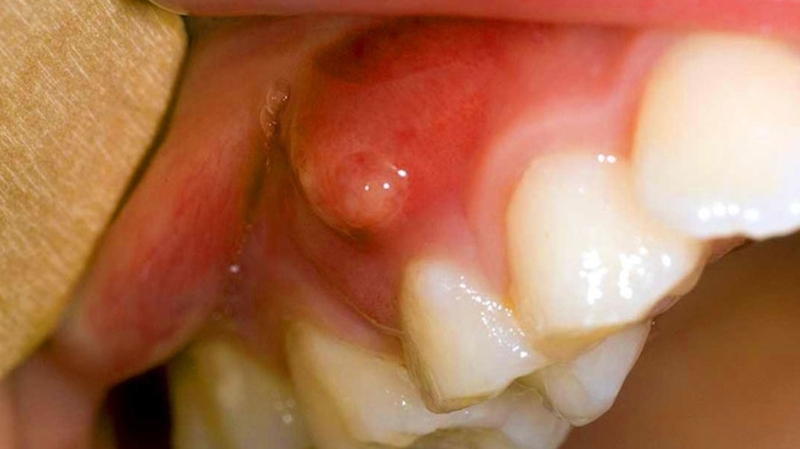

Mọc mụn ở lợi chân răng không chỉ gây đau nhức, khó chịu, hơi thở có mùi mà còn gây ảnh hưởng đến sức khỏe răng miệng. Vì vậy, cần được phát hiện và điều trị triệt để tình trạng này càng sớm càng tốt.

Mọc mụn ở lợi chân răng là một vấn đề rất phổ biến và đáng lo ngại đối với nhiều người. Nó có thể gây ra rất nhiều khó chịu và đau đớn, đặc biệt là khi bạn ăn hoặc chải răng. Tuy nhiên, bạn không cần phải lo lắng quá nhiều vì vấn đề này có thể được giải quyết và điều trị hiệu quả.

Mụn ở lợi chân răng thường xuất hiện khi có sự cố về răng miệng như mắc cài, nhiễm trùng nướu, côn trùng cắn, vết thương hoặc tổn thương khác ở vùng miệng. Mụn cũng có thể do vi khuẩn, nấm hoặc virus gây ra.